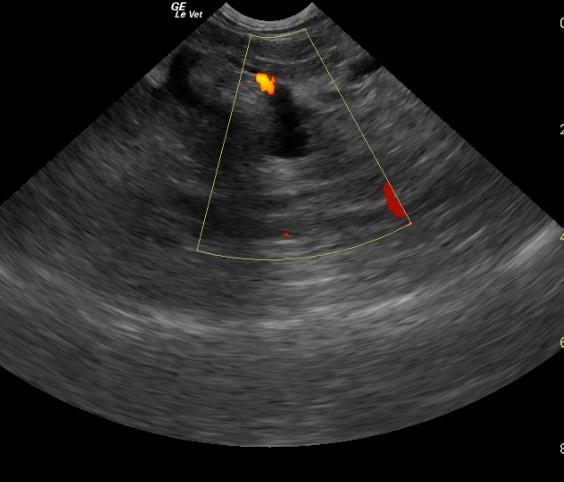

A 14-year-old MN DSH cat was presented for anorexia and lack of defecation. On physical examination, the eyes were sunken and the abdomen was soft and doughy. CBC showed leukocytosis, neutrophilia, lymphopenia, monocytosis, eosinopenia, and mild thrombocytosis. The only pertinent finding on blood chemistry was hyperglycemia. T-4 was within normal range. The patient was treated with subcutaneous fluids and force-fed A/D. Two days later the patient was hospitalized and treated with I.V. fluids, antibiotics, and supportive care. SPEC FPL result was high.

A 14-year-old MN DSH cat was presented for anorexia and lack of defecation. On physical examination, the eyes were sunken and the abdomen was soft and doughy. CBC showed leukocytosis, neutrophilia, lymphopenia, monocytosis, eosinopenia, and mild thrombocytosis. The only pertinent finding on blood chemistry was hyperglycemia. T-4 was within normal range. The patient was treated with subcutaneous fluids and force-fed A/D. Two days later the patient was hospitalized and treated with I.V. fluids, antibiotics, and supportive care. SPEC FPL result was high.